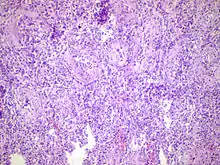

![]() | |

Acute epididymitis with abundant fibrinopurulent exudate in the tubules. | |